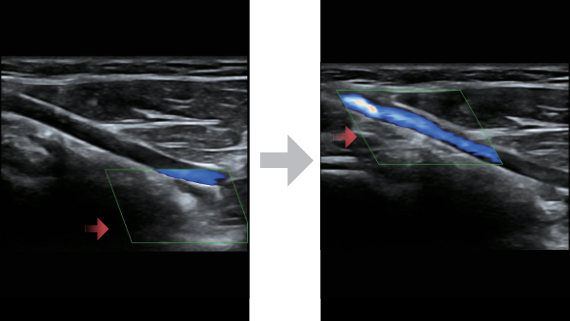

X-Insight ??? ??? ??? ??? ?? ??? ?? ?? ??????.

?????? ??? ???? ?? ???? ??? ??? ??? ???? ??? ??? ??? ?? ??? ???? ?????. ??? ?? ????? ???? ???? ??? ?? ??? ???? ?? ???? ??? ???? ???? ????.

???? ?? ??? ?????, X-Insight???? ??? DC-60 Exp ?? ??? ???? ???? ?? ??? ?? ??? ?? ???? ?????.

X-Insight??? ??? DC-60 Exp? ??? ??? ?? ?? ???? ???? ???(eXpress) ???, ???(eExceptional) ?????, ???? (eXceeding) ?? ??? ?? ????, ??? ???? ??? ??? ?? ???? ?????.